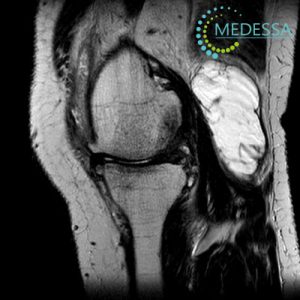

МРТ колінного суглоба – Кіста Бейкера або бурсит Бейкера

Кіста Бейкера, також відома як кіста синовіальної оболонки або бурсит Бекера, є аномалією, пов’язаною з суглобом, найчастіше з колінним суглобом. Ця кіста формується внаслідок накопичення суглобової рідини в задній частині коліна, утворюючи мішок або кісту.

МРТ надає докладні зображення м’яких тканин, кісток та суглобів, що дозволяє лікарям побачити структурні зміни в колінному суглобі, включаючи кісти, пошкодження хряща, запалення та інші аномалії.

4. Допомога у плануванні хірургічного втручання:

Якщо хірургічне втручання потрібне, МРТ може бути корисним інструментом для планування операції, визначення точного розташування кісти та оцінки структур навколо неї.